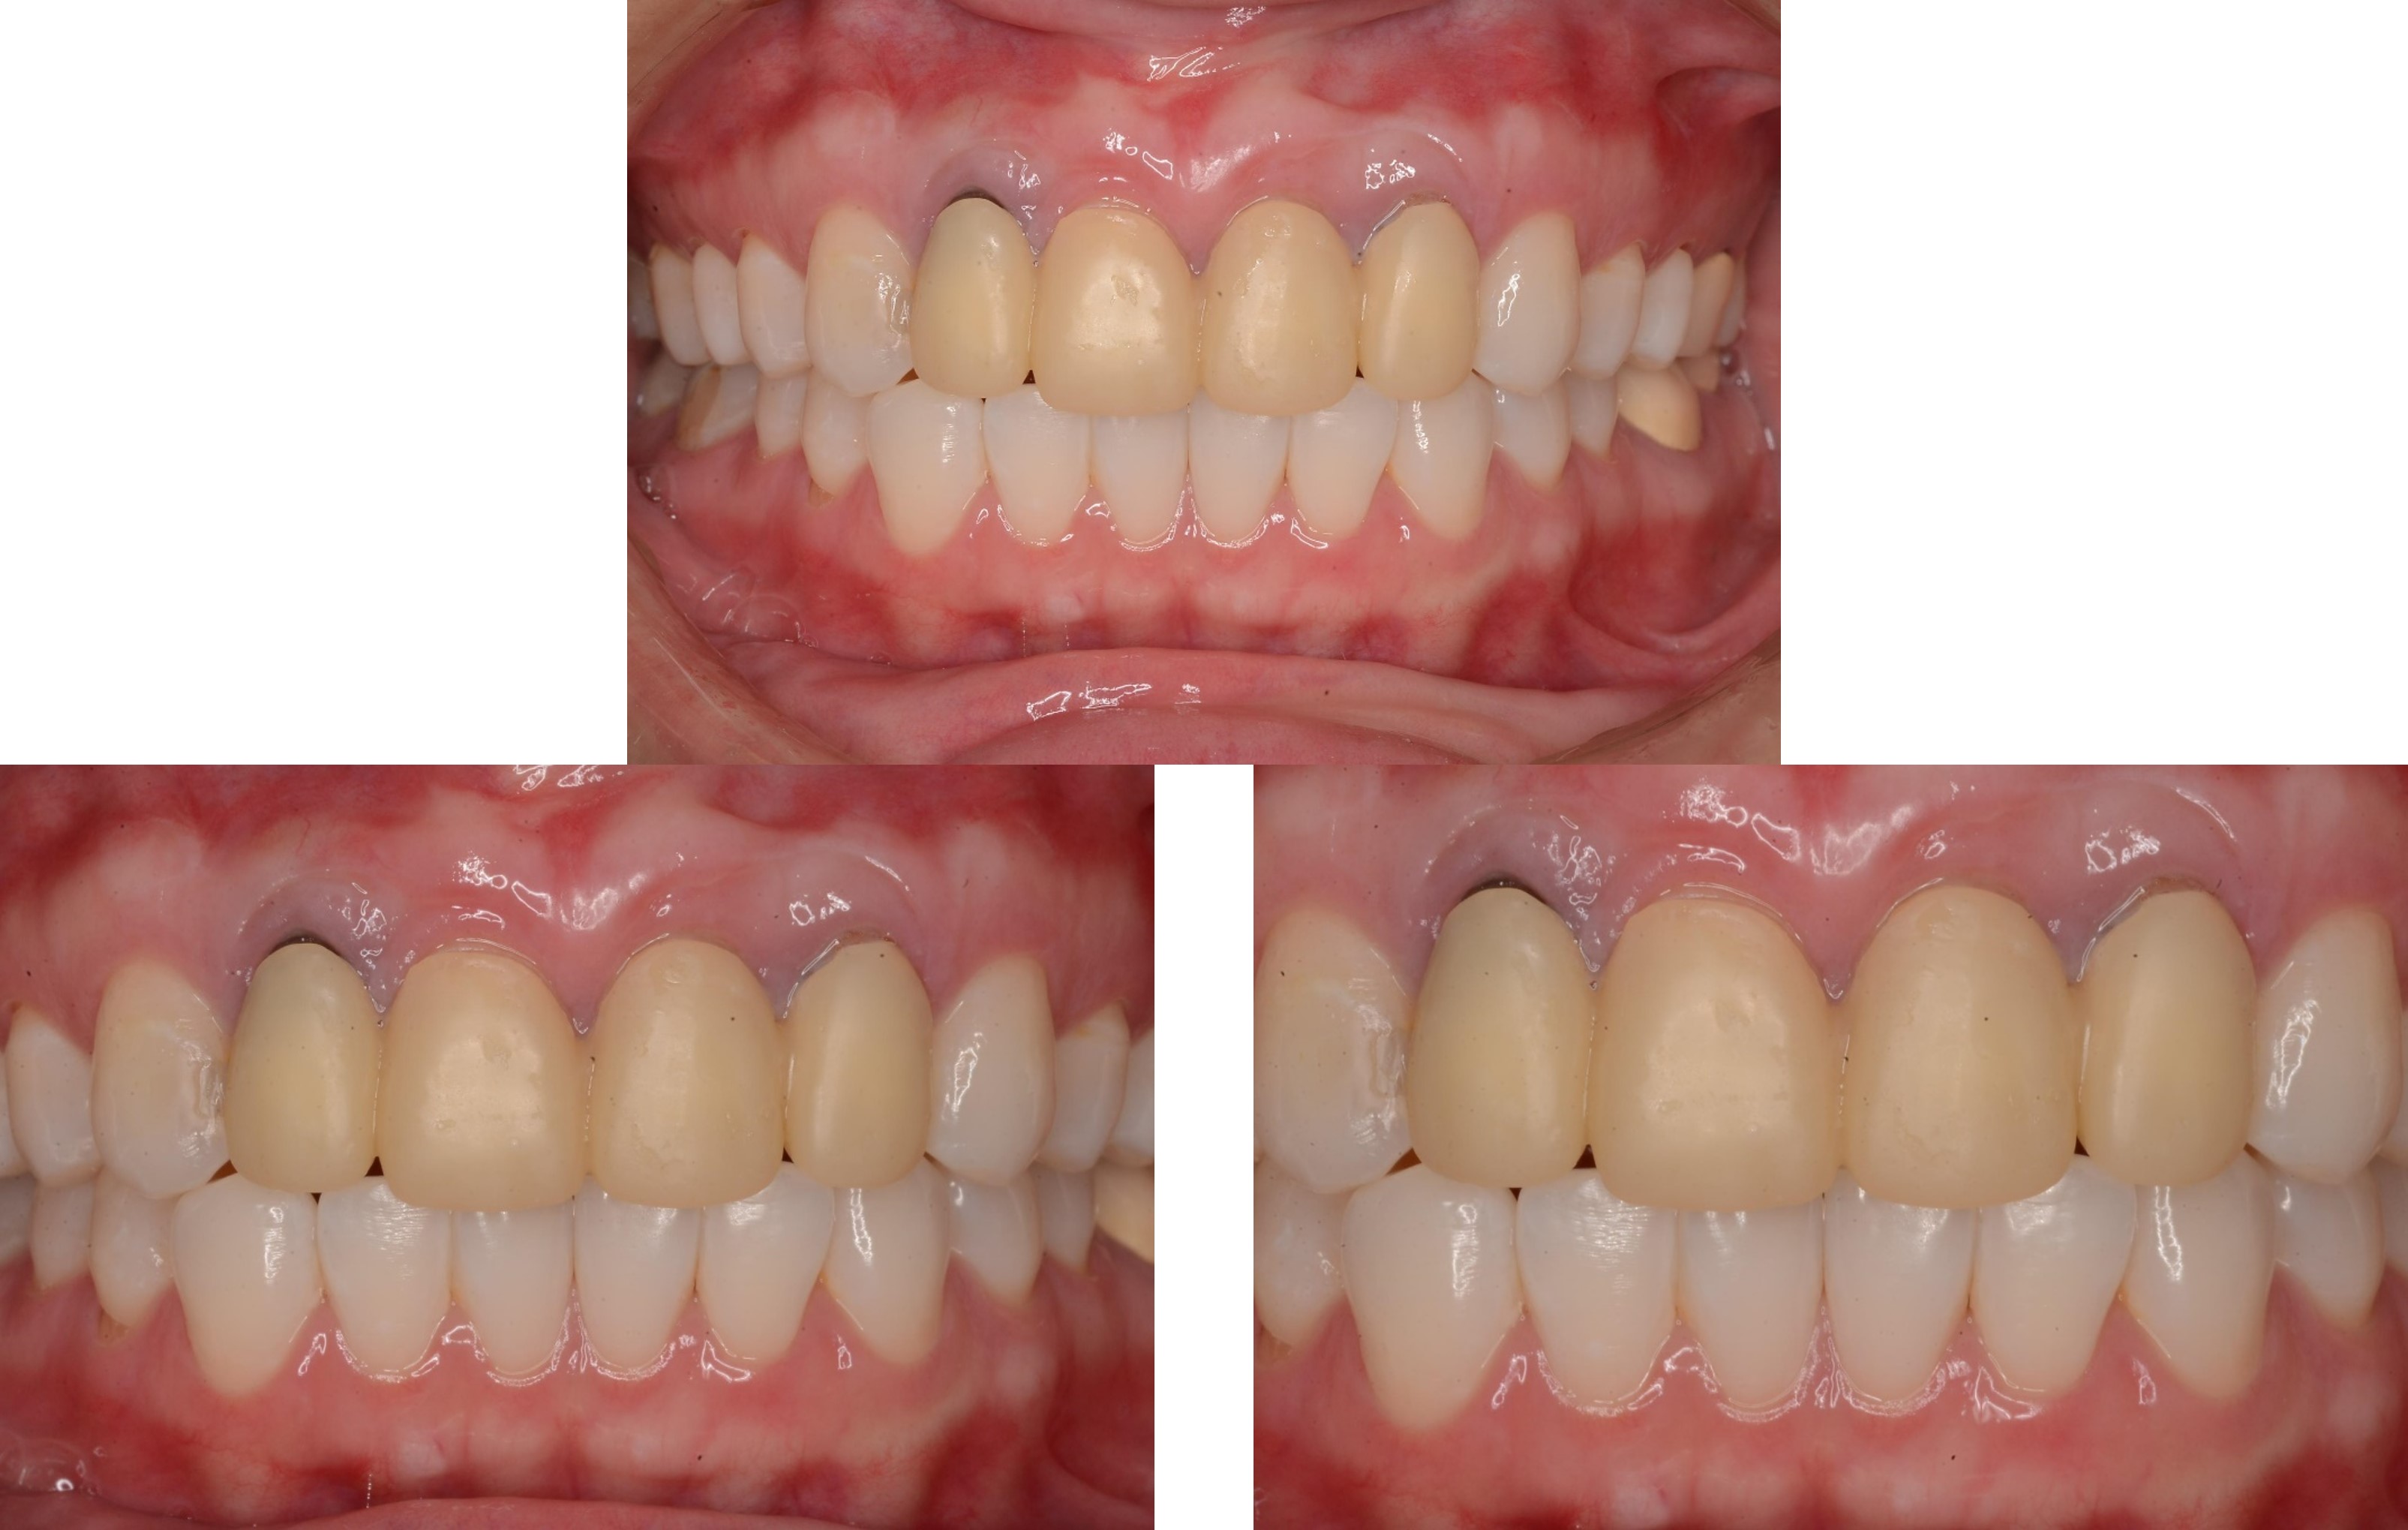

治療前,微笑時上牙不易容露出

美白前,牙齒預比色-B3

美白前,微笑分析

居家美白1個月後再評估-A1

前牙全瓷冠

前牙美觀與功能兼顧

微笑時,患者開心

術前、術後比較